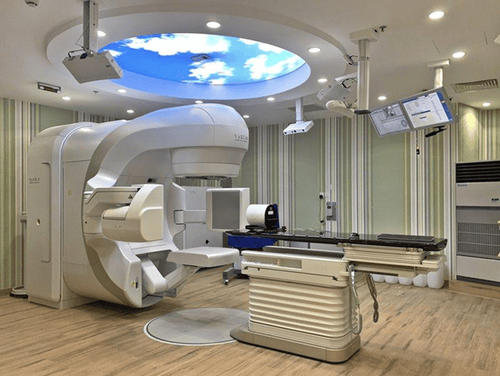

Các kỹ thuật viên có nhiệm vụ vận hành các máy xạ để thực hiện xạ trị theo chỉ định của bác sĩ và cung cấp cho bệnh nhân phương pháp xạ trị. Mặc dù bệnh nhân sẽ không gặp nhân viên lập kế hoạch và kỹ sư vật lý, nhưng đây là những thành viên quan trọng của nhóm lên kế hoạch điều trị xạ trị.

Lập kế hoạch trong quy trình xạ trị thường được thực hiện trên một máy quét CT, được gọi là CT mô phỏng. Nhờ vào hình ảnh từ CT mô phỏng, bác sĩ có thể xác định chính xác vị trí cần xạ.

Trước mỗi lần điều trị, các kỹ thuật viên xạ trị sẽ hướng dẫn bệnh nhân vào phòng điều trị và đảm bảo rằng tư thế nằm đúng vị trí để nhận các tia xạ hiệu quả nhất. Sau khi kiểm tra mọi thứ, các kỹ thuật viên xạ trị sẽ rời khỏi phòng trong một khoảng thời gian ngắn để bắt đầu điều trị.

Các kỹ thuật viên xạ trị sẽ theo dõi quá trình qua màn hình truyền hình và có thể nói chuyện với bệnh nhân thông qua một máy liên lạc. Bệnh nhân có thể yêu cầu nhân viên y tế mở nhạc yêu thích của mình để nghe trong khi đang được điều trị. Mỗi lần điều trị có thể kéo dài từ 10 đến 20 phút. Trong quá trình điều trị, việc quét hoặc chụp X-quang sẽ thường xuyên được thực hiện để theo dõi vị trí của người bệnh và vùng cơ thể đang được điều trị.